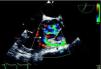

Transthoracic and transesophageal echocardiography revealed a restrictive subpulmonary ventricular septal defect (VSD) and infundibular pulmonary stenosis (Figure 1 and Video 1), with multiple vegetations related to the VSD involving the right coronary cusp of the aortic valve and protruding into the right ventricular outflow tract (RVOT) (Figure 2 and Videos 2 and 3). Vegetations were also observed adhering to the pulmonary valve and the pulmonary artery wall, probably due to jet lesion (Figure 3 and Video 4). A diagnosis of infectious endocarditis was made and the patient underwent surgery for removal of the vegetations (Figure 4), VSD closure, enlargement of the RVOT and pulmonary valvuloplasty without use of prosthetic material. His postoperative course was good, with no significant residual lesions, and there were no signs of heart failure or recurrence of endocarditis after two years of follow-up.